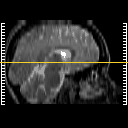

Click on sagittal image to select slice. Click on thin tickmark to change timepoint, or thick tickmark for overlay.